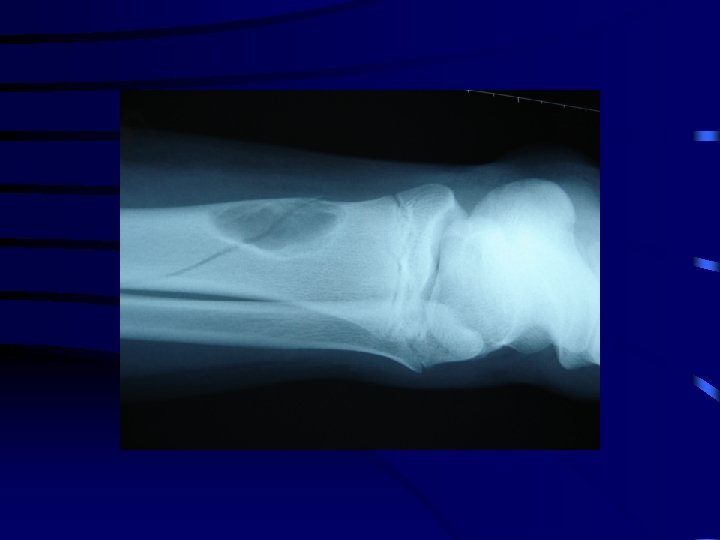

3 La fracture en motte de beurre • Il s'agit d'un tassement métaphysaire par impaction de la diaphyse dans la métaphyse. • L'exemple le plus fréquent est celui de la métaphyse inférieure du radius. • Il n'y a pas de risque de déplacement secondaire et une simple immobilisation antalgique est généralement nécessaire.

La fracture en motte de beurre